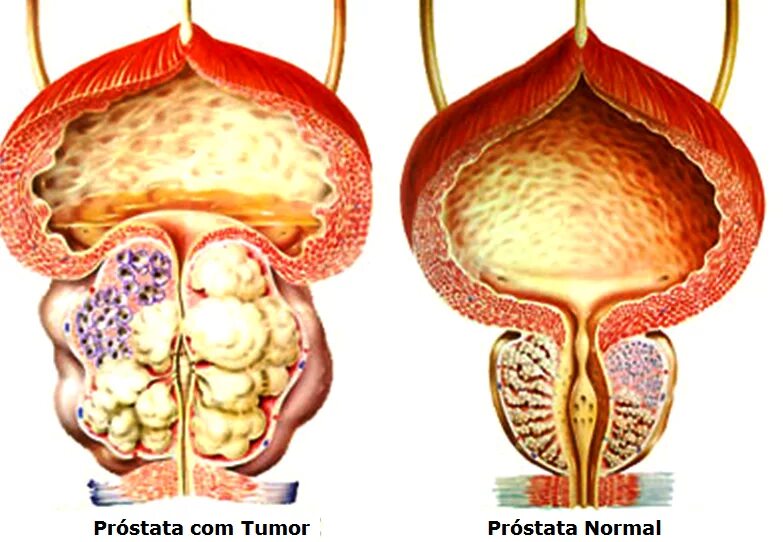

Анатомия аденомы предстательной железы. Эктопия предстательной железы. Злокачественная опухоль предстательной железы. Злокачественная аденома предстательной железы

Анатомия аденомы предстательной железы. Эктопия предстательной железы. Злокачественная опухоль предстательной железы. Злокачественная аденома предстательной железы Карцинома 4 степени предстательной железы. Онкология предстательной железы. Опухоль предстательной железы стадии

Злокачественная опухоль предстательной железы. Злокачественные новообразования простаты. Карцинома предстательной железы. Стадии опухоли простаты Опухоль предстательной железы стадии. Стадии онкологии предстательной железы. Стадии аденомы предстательной железы

Опухоль предстательной железы стадии. Стадии онкологии предстательной железы. Стадии аденомы предстательной железы

Опухоли предстательной железы классификация. Злокачественное новообразование предстательной железы. Опухоль предстательной железы т2. Стадии ЗНО предстательной железы

Опухоли предстательной железы классификация. Злокачественное новообразование предстательной железы. Опухоль предстательной железы т2. Стадии ЗНО предстательной железы Опухоль предстательной железы пса. Что такое РПЖ предстательной железы. Степени опухолей простаты. Предрак предстательной железы